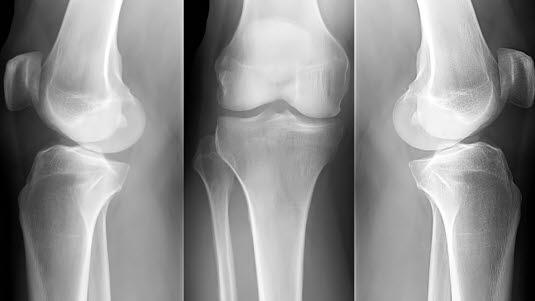

Artrografi er en røntgenundersøkelse av et ledd i kroppen etter innsprøyting av kontrastvæske i leddet. Undersøkelsen gir bilder av det indre av leddet. Artrografi benyttes først og fremst i undersøkelsen av kneledd, skulderledd, hofteledd, albueledd, håndledd, kjeveledd.

Ved en normal undersøkelse fylles leddet greitt med kontrastvæske og man får en normal framstilling av strukturene på innsiden av leddkapselen: Leddspalte, slimposer, eventuelle menisker (kneleddet), leddbånd og leddbrusk.

De vanligste funnene er forandringer forenlig med leddbetennelse (artritt), leddbåndskader, meniskskader i kneleddet, forandringer i leddhinnen (synovitt), trangere leddspalte og cyster.